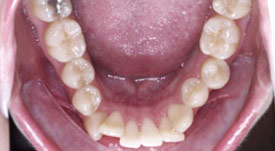

Crowding Lower